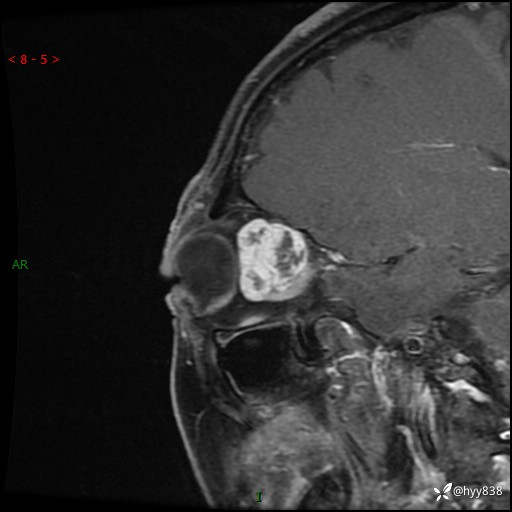

老年女性,右眼球突出1月。说说鉴别诊断,看谁第一个秒---(有结果)

主诉:发现右眼球突出1月余

简要病史:患者于1月前无明显诱因发现右眼球突出,偶感磨痛、眼胀,无视力下降,无头痛,恶心呕吐等不适。10天前就诊于当地县人民医院就诊,完善头颅ct检查,诊断为右侧眼眶肿物,建议患者上级医院进一步治疗,患者因个人原因拒绝。拟行手术,来我院就诊,门诊行相关检查后以“右眼眼眶肿物”收入院。 患病以来,患者精神饮食睡眠尚可,大小便如常、体重无明显改变。

辅助检查:MRI

临床诊断:眼眶肿物

眼眶MRI平扫+增强